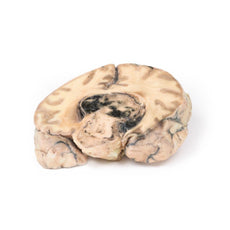

3D Printed Left Cerebral Infarct

The patient was a 51-year old woman who had a cerebro-vascular accident resulting in a left

hemiplegia 2 years prior to death. At necropsy, she had severe generalized atherosclerosis and an old left

ventricular myocardial infarct with an overlying mural thrombus.

A coronal section of the cerebral hemispheres shows irregular cystic cavities in the territory of

distribution of the right middle cerebral artery. The cavities of the infarct have irregular, yellow walls and

show partial collapse. There is compensatory dilatation of the left lateral ventricle. On the posterior aspect,

the arteries below the mammillary bodies were moderately atheromatous, although this is difficult to visualise

macroscopically.

Because of the underlying history of myocardial disease with the presence of the mural

thrombus, it is assumed that her cerebral infarct was probably caused by a thromboembolus.